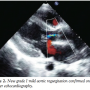

After confirming precise position of the device on transthoracic echocardiography and control angiography, the rest of the device was deployed on the pulmonary arterial side, by withdrawing the delivery sheath. Post-release angiogram revealed no residual shunt. However, there was new grade I mild AR (Figure 1B) that was also confirmed on color doppler echocardiography (Figure 2). Clinically no murmur was audible and aortic pulse pressure had decreased as well as pulmonary artery pressure (Aortic pressure 112/72 mmHg; pulmonary artery pressure 40/25 mmHg; mean 33 mmHg). As the defect was remote from aortic valve and there was no impingement on it, the result was accepted. On follow-up at 3 months and 6 months, patient was asymptomatic. Importantly, there was a progressive decrease in the grade of AR from mild to only trivial grade at 6 months (Figure 3).

The new aortic regurgitation tends to disappear on follow-up. We have encountered similar aortic regurgitation detected on color doppler echocardiography during transcatheter closure of ruptured sinus of Valsalva aneurysm too, as reported recently.4